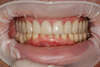

Situation dents provisoires en place